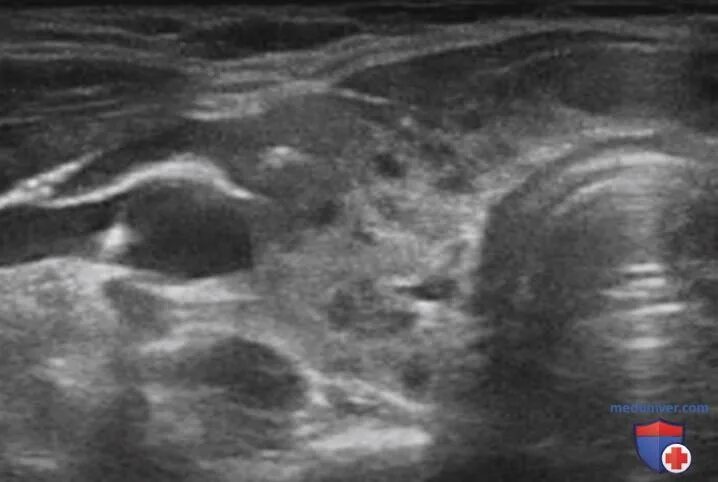

Диффузное увеличение железы